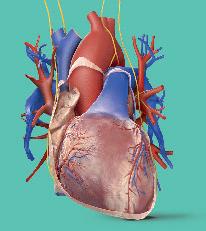

Lidé kdysi věřili, že srdce je sídlem myšlení a citu, dnes však víme, že je to svalová pumpa, která neúnavně pracuje, aby udržela krev v pohybu.

Na rozdíl od jiných svalů v těle, které si po námaze potřebují odpočinout a na chvíli se zastavit, je srdce předurčeno pracovat nonstop. Bije 70krát za minutu, 100 000krát za den, 40milionkrát za rok a za průměrný život napumpuje tolik krve, že by naplnila tři obří tankery. S každým úderem vytlačí okolo jednoho plného šálku krve a vyvíjí dostatečnou sílu, aby udrželo proudění krve ve 100 000 km cév v těle. Nepřetržitá dodávka čerstvé krve je pro tělní buňky životně důležitá, protože bez ní by během pár minut zahynuly na nedostatek kyslíku.

Uvnitř srdce

Srdce je rozděleno na dvě poloviny, takže pracuje jako dvě pumpy v jedné. Pravá polovina pumpuje odkysličenou krev do plic, aby zde nabrala vzdušný kyslík. Levá polovina pumpuje okysličenou krev do těla.

Srdeční cyklus

Každý úder srdce se skládá z několika pečlivě načasovaných kroků. Celá sekvence je řízena elektrickými impulsy, které se rychle šíří srdeční svalovou stěnou a spouštějí kontrakci svalových buněk.

1 Plnění

Mezi stahy vstupuje krev žilami do srdce a shromažďuje se v horních prostorách (síních).

Pravá síň se stahuje. Levá síň se stahuje.

Krev je tlačena do komor.

Věnčité tepny

Srdce pumpuje krev nejen do těla, ale do své vlastní svalové stěny. Srdeční sval velmi těžce pracuje a potřebuje vydatný přísun okysličené krve.

Poté, co dodá do svalové srdeční stěny kyslík a palivo, odtéká použitá krev žilami (znázorněnými modře).

Krev vracející se z těla. Krev vracející se z plic.

2 Síně se stahují Horní prostory se stahují a tlačí krev chlopněmi do dvou spodních prostor (komor).

proudí do těla. Krev proudí do plic.

3 Komory se stahují Nakonec se s velkou silou stahují komory a vytlačují krev do všech částí těla.